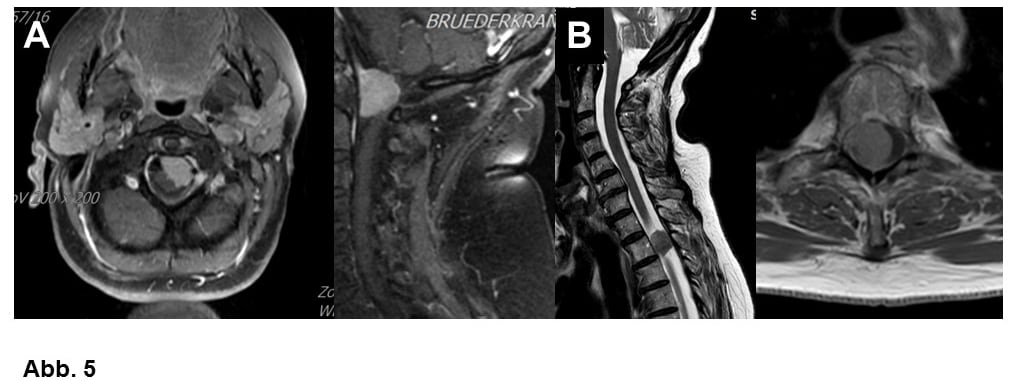

Von großer klinischer Bedeutung ist die Einteilung nach Lokalisation. Am häufigsten wachsen Meningeome ausgehend von der Hirnhaut über den Hemisphären (= Hirnhälften, Konvexitätsmeningeome, Abb. 1A-C) oder im Bereich einer bindegewebigen Sichel zwischen den Hemisphären (Falxmeningeom, Abb. 1C und D). Sogenannte Schädelbasismeningeome (Abb. 2, 3 und 4C) sind wegen ihrer Lage häufig schwieriger zu operieren als Konvexitäts- und Falxmeningeome. Meningeome können nicht nur ausgedehnt in den Hirnhäuten, sondern auch im Knochen (Abb. 4A und B) oder sogar vom Knochen ausgehend in die umgebenden Weichteile einwachsen (Abb. 4C). Meningeome im Bereich der Wirbelsäule (Abb. 5) sind seltener als im Kopf, sind aber umgekehrt häufige Tumoren im Rückenmarkskanal, wo sonst Tumoren eher selten sind. Bei bis zu 20% der Patienten liegen mehrere Meningeome vor (Abb. 1C).

Meningeome treten häufiger bei Frauen als bei Männern auf, das ist bei Meningeomen der Wirbelsäule besonders auffällig (Abb. 5). Eine überzeugende Erklärung dafür gibt es nicht. Männer erkranken relativ häufiger an WHO Grad II- oder III-Tumoren (Abb. 4B, 6A und B). Ionisierende Strahlung gilt als wichtiger Risikofaktor, so haben zum Beispiel Patienten, die als Kinder bei Leukämie eine Schädelbestrahlung erhalten haben, ein vielfach erhöhtes Risiko, an einem Meningeom zu erkranken. Welche Genmutationen (Veränderungen der Erbsubstanz) zur Meningeomentstehung führen, ist derzeit Gegenstand intensiver Forschung. Es konnten bereits mehrere Meningeomgene identifiziert werden und man muß damit rechnen, dass solche Befunde zukünftig ähnlich wie bei den Gliomen für die Diagnostik und Behandlung von Meningeomen wichtig werden. Vererbt werden diese Veränderungen aber nicht.

A. Meningeom am Hinterhauptsloch, 62-jährige Frau.

B. Meningeom im Rückenmarkskanal, 78-jährige Frau. Trotz der sehr deutlichen Verdrängung des Rückenmarks sind solche Tumoren meist gut zu operieren.